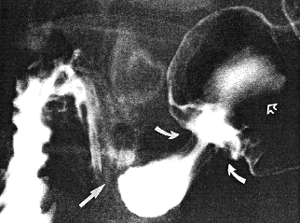

![]() |

| Fig. 13.2. Four monophasic duodenal pressure waves. Each was associated with a radiologically visible contraction. During each wave mucosal folds changed in direction to become longitudinal. Base line indicates intraluminal pressure in absence of motor activity. Ten-second marker on zero line |